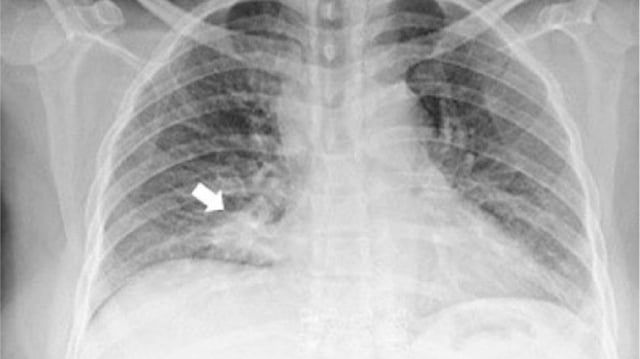

بعد ذلك، جاء الكشف، عن طريق الأشعة السينية للصدر والأشعة الشاملة للجسم، عن وجود كتلة خبيثة مختبئة في المنطقة السفلية من رئتها اليمنى، مع محلاق من الأنسجة السرطانية تمتد إلى أعضاء مختلفة، بما في ذلك المشيمية العينية.

كتلة خبيثة في المنطقة السفلية من رئة المريضة Elsevier